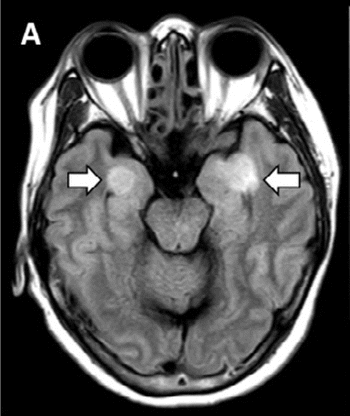

Scans show greater amyloid accumulation in the brains of older adults who get less than six hours sleep nightly.

CT and MRI scans show neurological impacts.